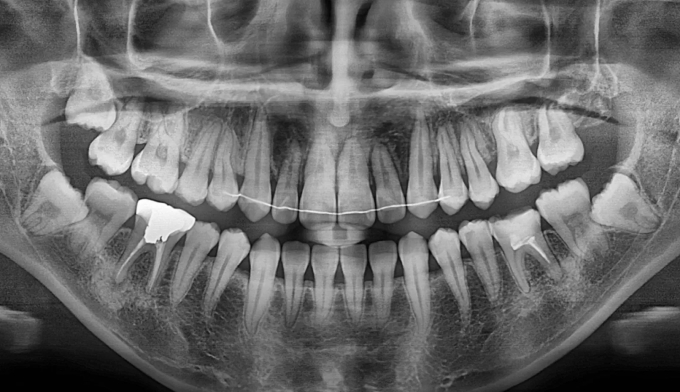

어금니가 선천적으로 없는 경우, 어금니 사이에 공간이 유지된 채 악골의 성장이 완료됩니다. 벌어진 어금니 공간은 음식물이 잘 끼게 되므로, 충치가 생길 수 있는 가능성이 높아지고 냄새가 나기도 합니다.

이때, 이러한 공간을 벌려서 임플란트를 식립하는 방법이 우선적으로 고려됩니다. 하지만 후방에 사랑니가 위치한 경우, 임플란트 대신 사랑니를 당겨서 쓰게 되면 내 치아를 살리면서 동시에 임플란트라는 인공 구조물을 식립하지 않아도 되기 때문에 교정치료가 훨씬 효율적인 치료가 됩니다.

교정기간은 8개얼 소요되었고, 안적적으로 유지하기 위해 일정기간동안의 유지장치 착용이 필수입니다.